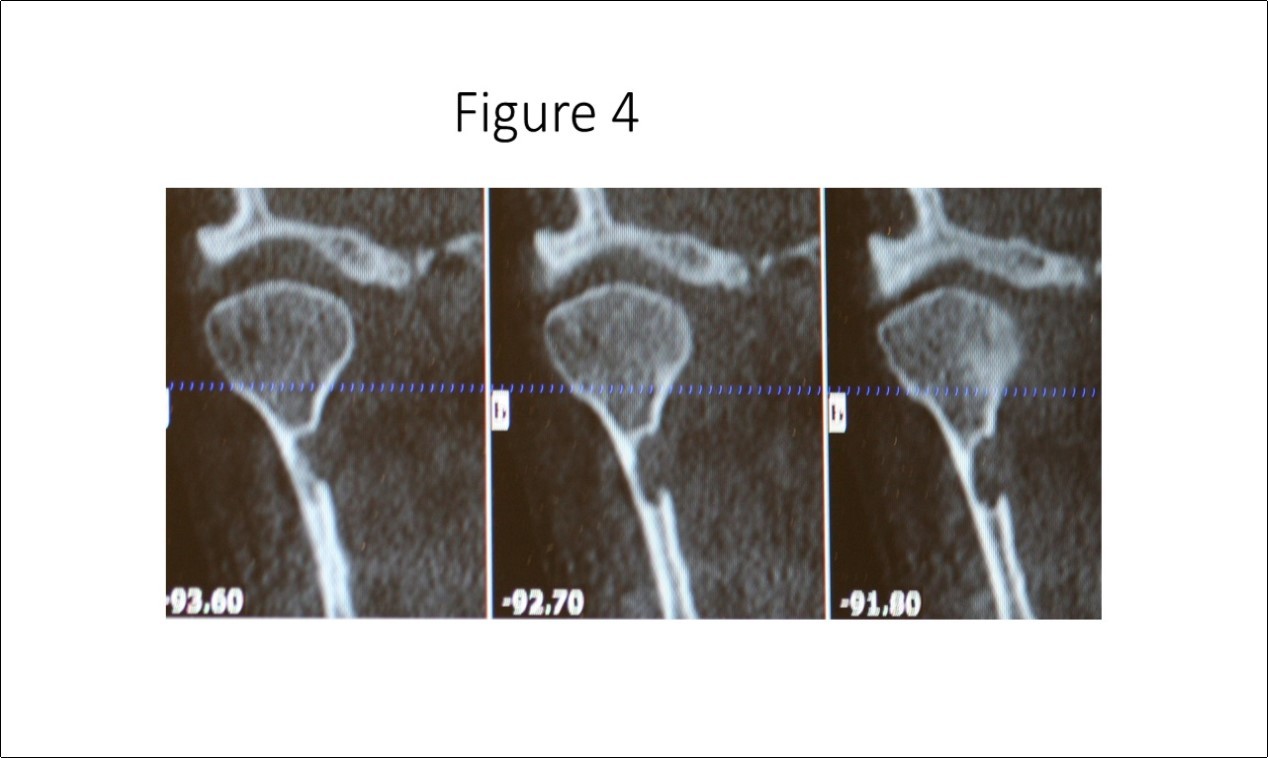

Maxillofacial examination was unremarkable. No facial swelling, masses or asymmetry was observed. The TMJ examination was normal. No pain or tenderness to digital palpation was observed in the right preauricular region. Oral examination of the patient was unremarkable. No trismus was observed as the maximal interincisive opening was greater than 40.0mm. No anterior or posterior open bite was observed. Imagining studies to rule-out intraosseous neoplastic lesions and arrive at a definitive diagnosis consisted of a panoramic radiograph and cone beam CT scan (120 kVp, 5 mA, 7.4 sec). Panoramic radiograph revealed a unilocular, well-circumscribed radiolucency in the right subcondyalar region of the mandible that was close to the posterior border of the condylar neck (Figure 2). Cone beam CT scan (i-CAT FLX, Imaging Sciences, Hatfield, PA) imaging revealed a well-defined unilocular, elliptical shaped radiolucent lesion on the medial surface of the right subcondylar neck of the mandible (Figure 3, Figure 4, Figure 5). The elliptical shaped unilocular lesion involved almost the entire horizontal dimension of the subcondylar neck (Figure 4). Figure 5 shows the three-dimensional CT scan reconstruction (i-CAT FLX, Imaging Sciences, Hatfield, PA) of the medial defect in the subcondylar region of the mandible. Based on knowledge of clinical head and neck anatomy and imaging studies, no treatment was indicated as the diagnosis was consistent with a variant of a Stafne bone cavity of the right subcondylar neck near the parotid gland and not a pathological condition. The patient was informed about the risk of condylar neck fracture due to the critical size of the SBC.

Figure 4.Cone beam CT TMJ sagittal views illustrate osseous defect on medial cortex. Note the thinness of the cortex that places the patient at risk for fracture of the condylar neck.